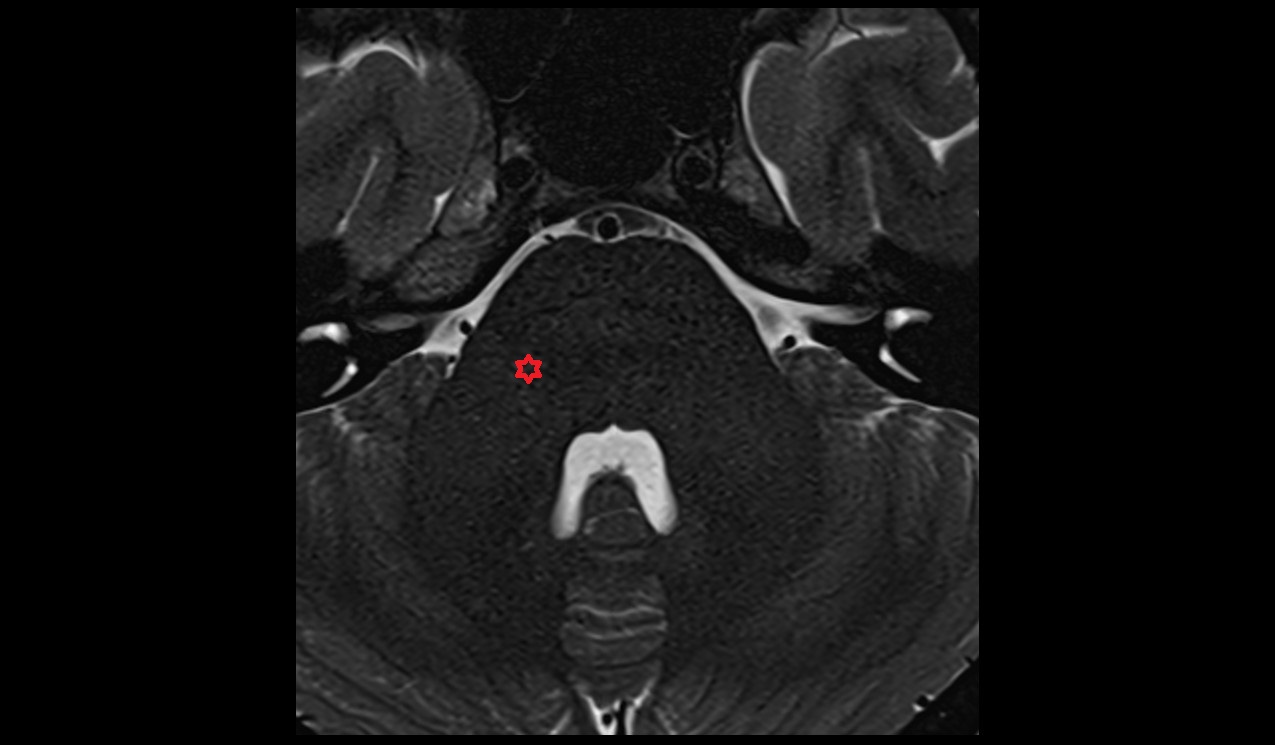

- Peripheral zone of prostate

- Anterior Fibromuscular Stroma of prostate

- Central zone of prostate

- Transitional zone of prostate